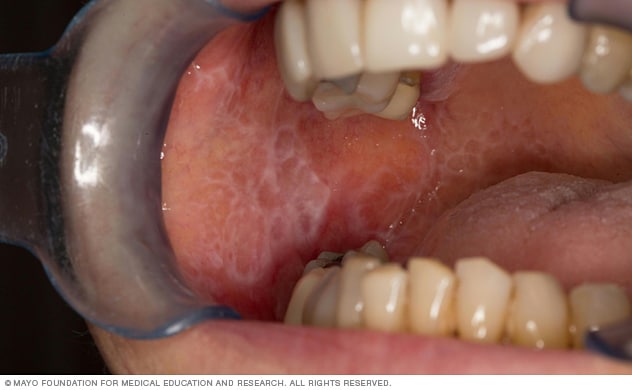

• Reticular. This type appears as white patches in the mouth and can look lacy. It's the most common type of oral lichen planus. It usually has no related symptoms. And it usually doesn't need treatment or lead to major complications.

• Reticular. This type appears as white patches and can look lacy.